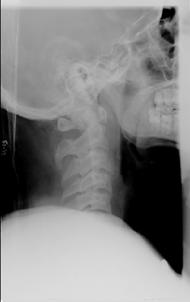

TRAUMA CERVICALA

Incidenta laterala Incidenta

laterala Incidenta

antero-posterioara